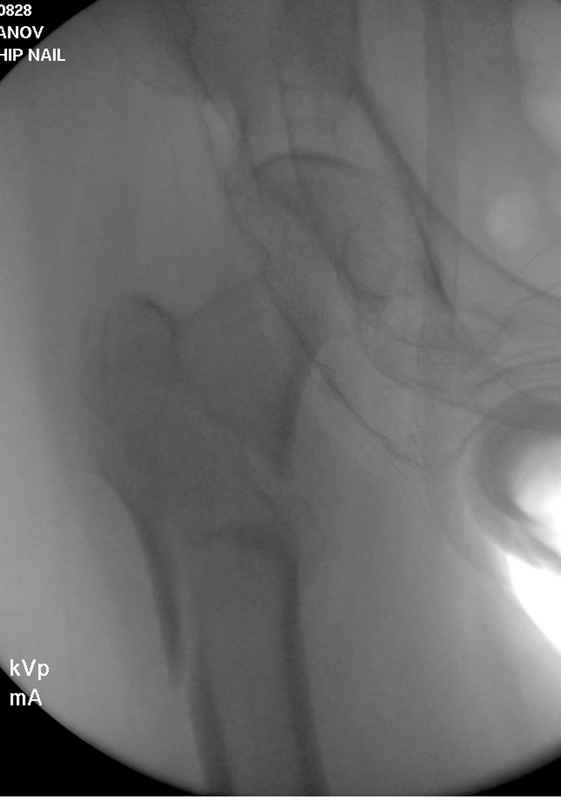

Здесь пара случаев фиксации похожих переломов:

первый высокоэнергетическая травма 36 лет